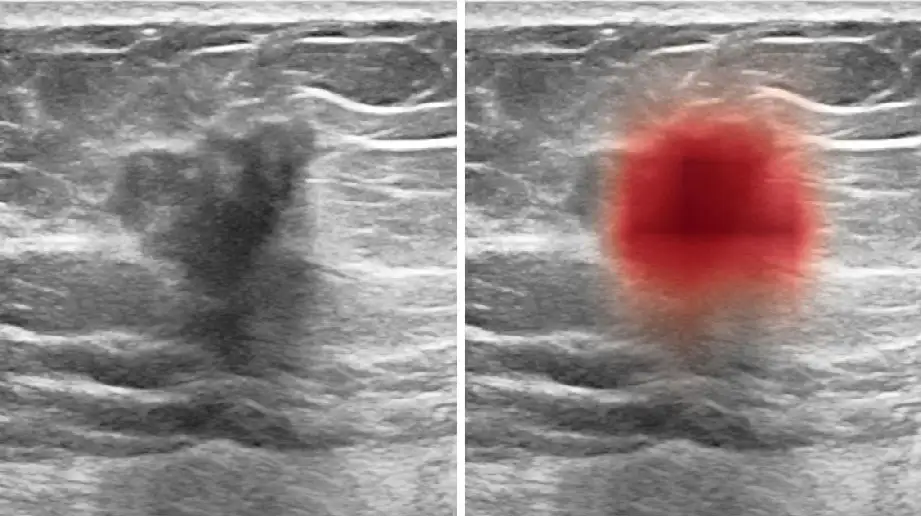

A computer program trained to see patterns among thousands of breast ultrasound images can aid physicians in accurately diagnosing breast cancer, a new study shows.